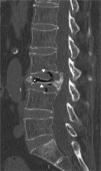

She consulted for low inflammatory back pain lasting 4 weeks, with no history of trauma, fever or constitutional symptoms. The lateral lumbar spine X-ray showed a fracture of L3 due to collapse with intravertebral vacuum phenomenon (IVVF), suggesting vertebral osteonecrosis (ON). Computed tomography (CT) and magnetic resonance imaging (MRI) confirmed this diagnosis (Figs. 1–3). Surgical fixation was performed of the area. The study showed histological signs of bone avascular necrosis: trabecular bone tissue with extensive areas of necrosis, medullary space with proliferation of granulation tissue, few hematopoietic elements, necrosis and cellular debris.

IVVF, although not pathognomonic, is the most characteristic radiographic sign of this entity and often suggests the diagnsis.3,4 This sign reflects the presence of gas within the bone (mainly nitrogen) and in adjacent tissues. IVVF can be seen in radiographs, a linear or crescent-shaped radiolucent image usually located adjacent to the superior endplate, which appears or is enhanced by the extension, and decrease or even disappears with flexion of the spine. Sometimes it can be detected by CT or MRI because of its greater sensitivity.